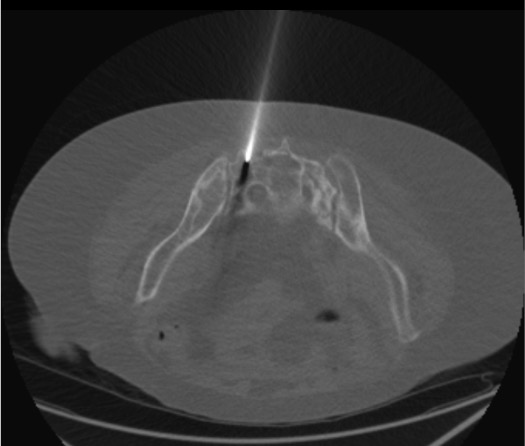

Trocar Insertion — Long-Axis Technique

Biplanar Fluoroscopic or CT Confirmation of Trocar Position

- Long-axis approach: needle enters through posterior sacral surface, angled medial-lateral and caudo-cranially into the alar intramedullary space, staying lateral to S1 foramen

Do not inject cement. Partially withdraw trocar under CT guidance. Redirect using adjusted medial-lateral and caudo-cranial angle. Confirm intramedullary position with CT before proceeding. The long-axis technique requires accurate angling — initial entry angle is the most critical step; small angular errors compound over the length of the alar.